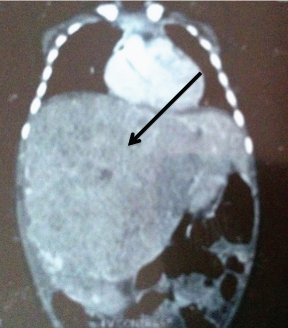

On examination, he was afebrile and had massive hepatomegaly; the spleen was not palpable and there was no lymphadenopathy. Routine haemogram showed moderate anemia (7.2 g/dl) and high ESR (46 mm/1st hour). Serum aspartate transaminase was 78 IU/ml, total bilirubin 1.6 mg/dl and indirect bilirubin 1.03 while Alpha Fetoprotein (AFP) was high (302ng/ml). Abdominal CT scan showed a large mass measuring 72 x 68 mm involving almost the entire liver [Table/Fig-1].

Pre treatment CT film showing massive hepatomegaly.